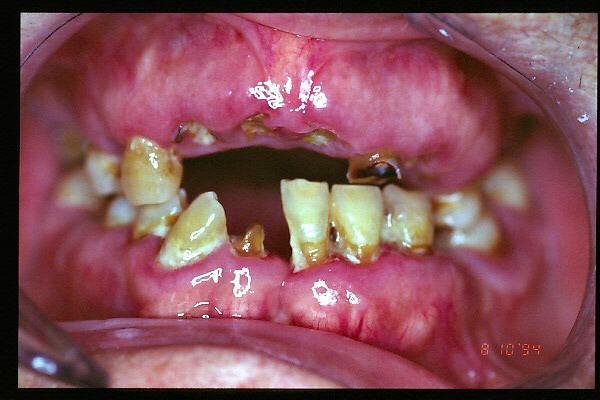

CM Enfermedad periodontal avanzada con caries. Mala higiene.